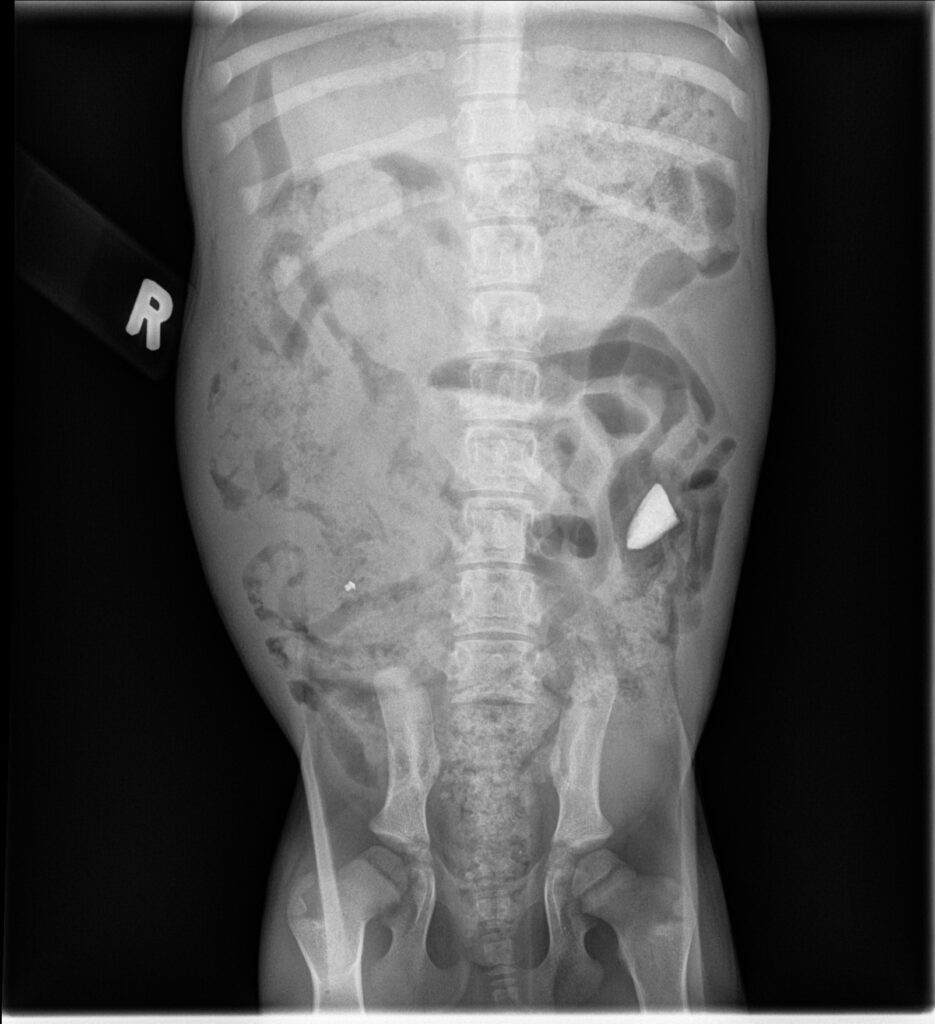

X-rays revealed a stomach full of rocks. Yes, rocks.

Over several days, vets kept an eye on the dog and it turned out, she was pooping out the rocks. So, no surgery was required.